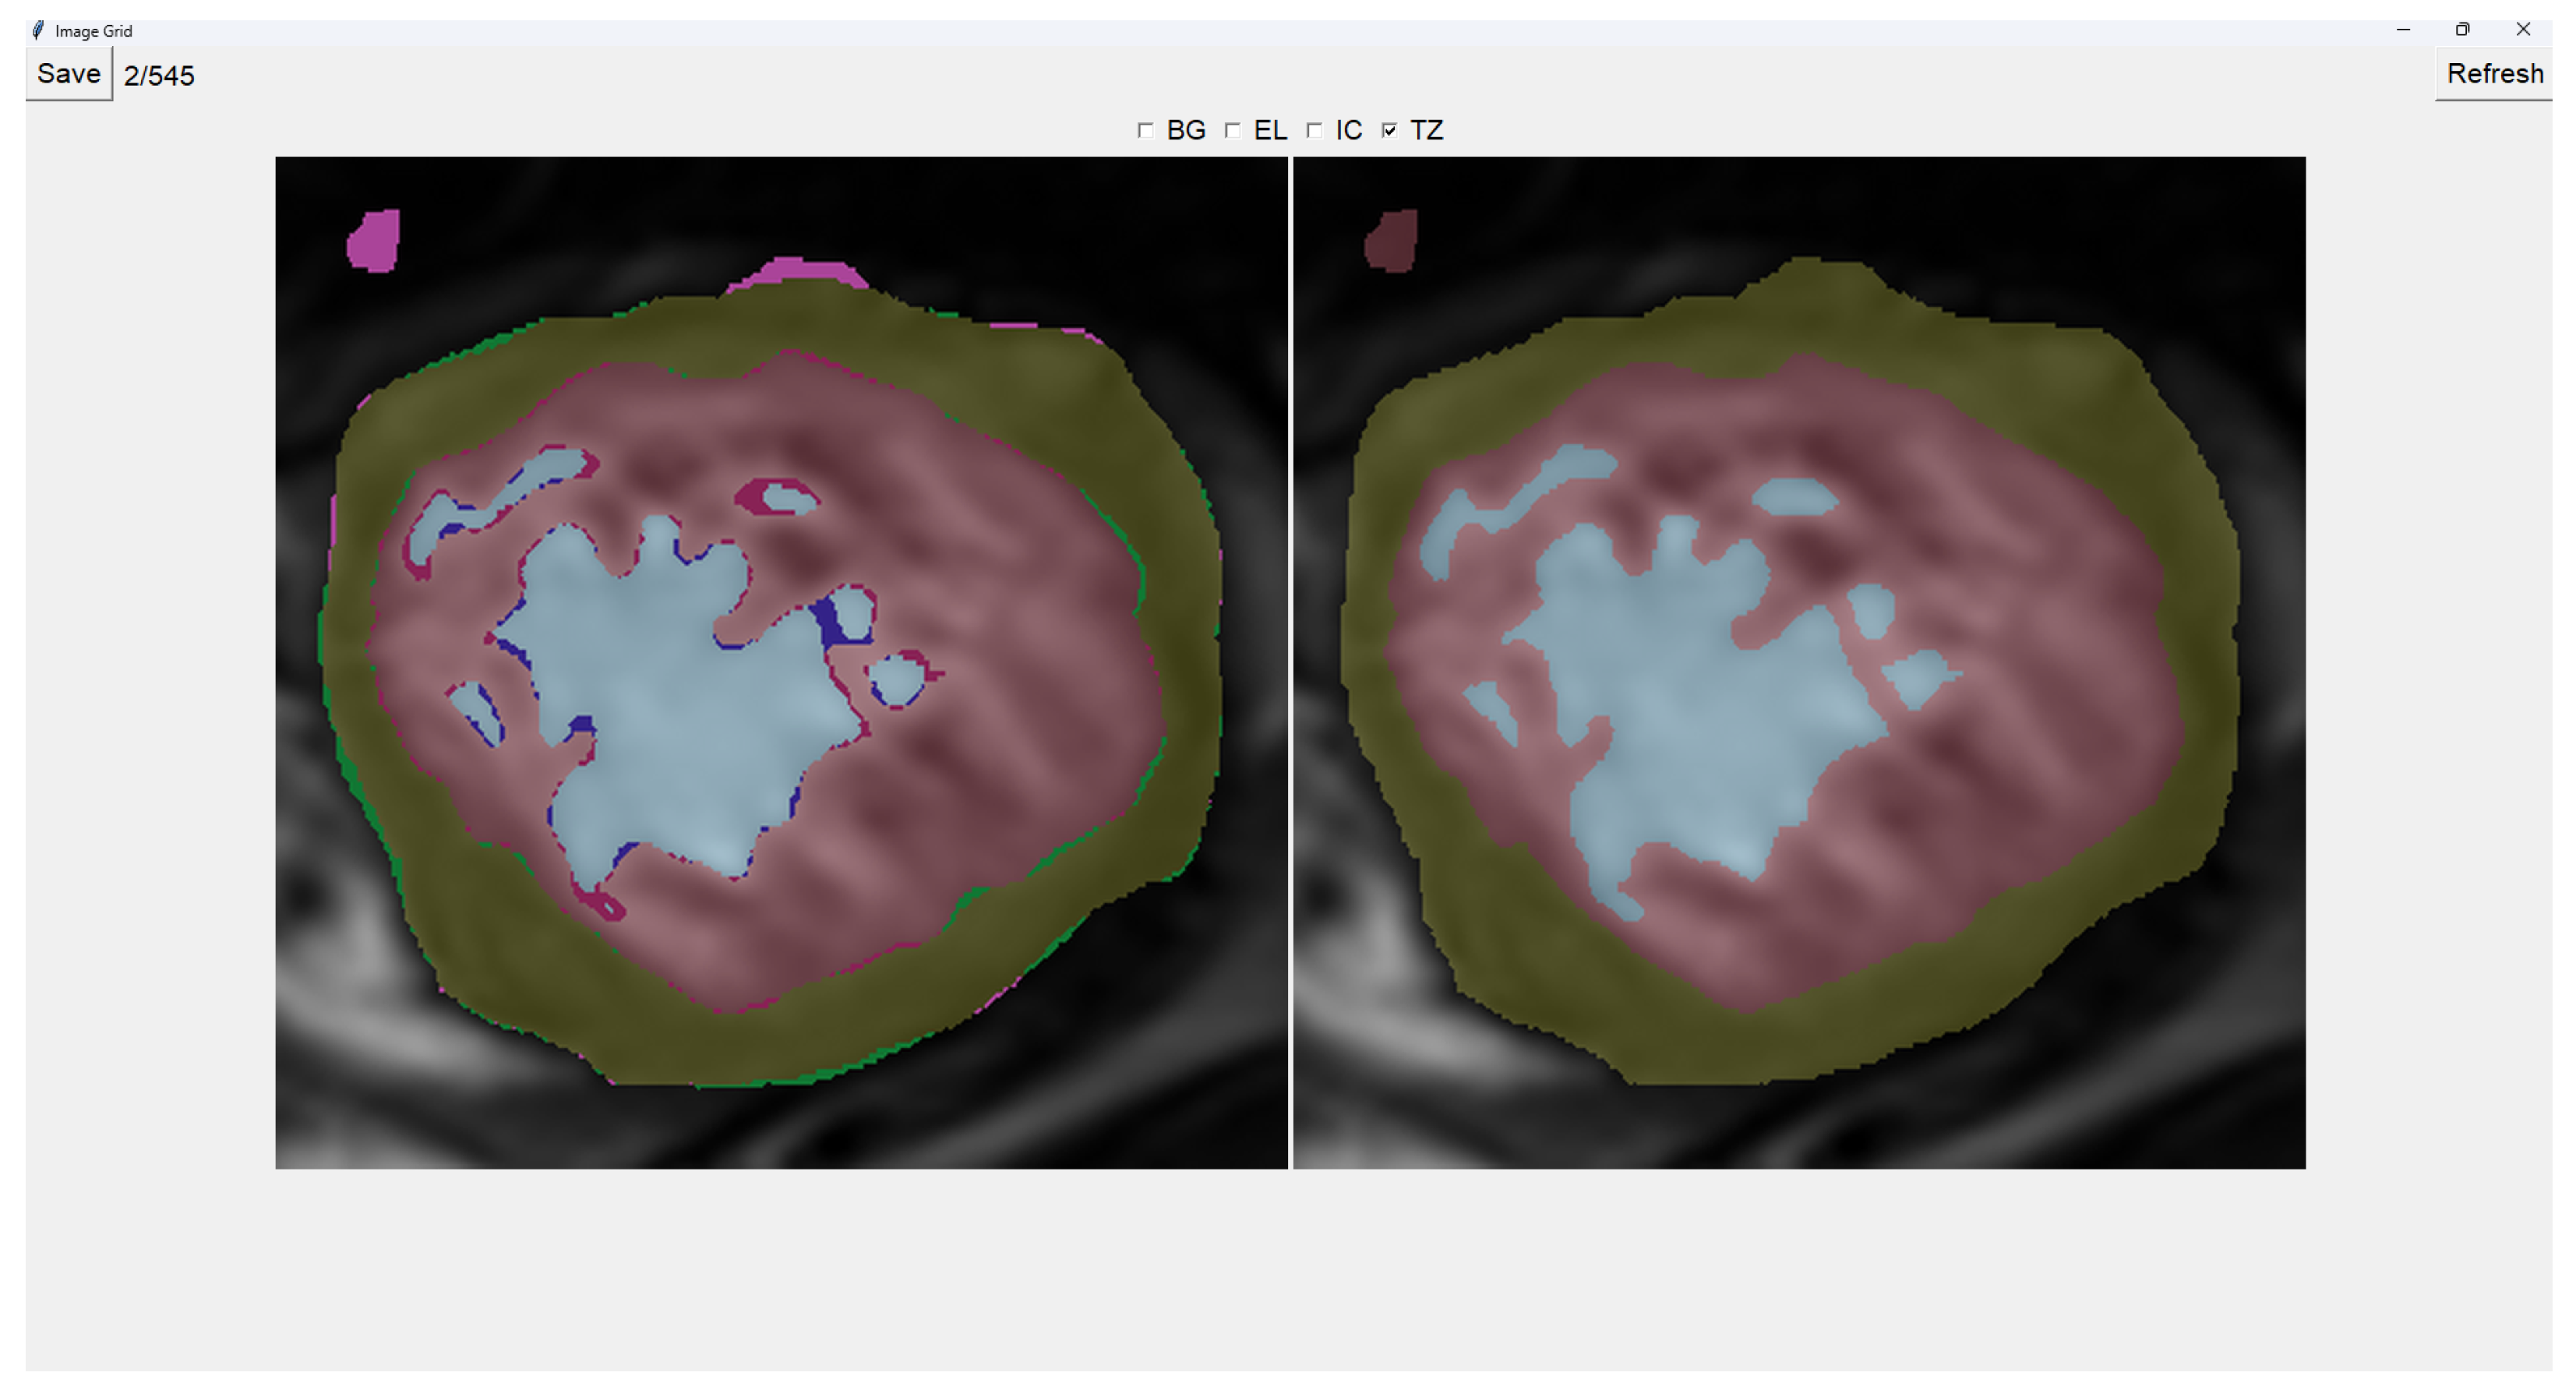

This program presents two images as shown in Figure 3. The image on the left is obtained from our previous method (QLVTHC), while the one on the right is obtained from our neural networks (Section 2.1). The final output of our program is the segmentation on the right.

We use a muted color scheme to make the colors distinguishable for colorblind people. In the image on the right, the External Layer is olive green, the Internal Cavity is cyan, and the Trabecular Zone is rose.

On the figure on the left, we mark the differences between both segmentations. This way, where there is an External Layer on the left and something else on the right, we mark it with green. For additional Internal Cavity, we mark it with blue; for Trabeculae, we mark it with wine red; for Background, we mark it with purple.

The differences between both images can be leveraged for easy transformations of the output image. The transformation is applied to the image on the right by simply clicking one of the differences. For example, if we click a blob that is colored green on the left (meaning an additional External Layer), an External Layer will appear in that zone of the image on the right. Some of these blobs are very small, so you can select them by right-clicking and dragging over them for ease of use.

Painting directly on the output image (the image on the right) is also possible. For this, we select either BG (Background), EL (External Layer), IC (Internal Cavity), or TZ (Trabecular Zone). Then, we simply left-click where we want to paint (as shown in Figure 4).